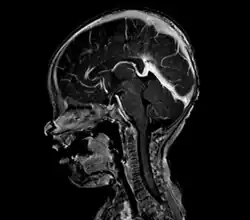

vein of Galen malformation

A cerebral AVM diagnosis is established by neuroimaging studies after a complete neurological and physical examination.[5][13] Three main techniques are used to visualize the brain and search for an AVM: computed tomography (CT), magnetic resonance imaging (MRI), and cerebral angiography.[13] A CT scan of the head is usually performed first when the subject is symptomatic. It can suggest the approximate site of the bleed.[3] MRI is more sensitive than CT in the diagnosis, and provides better information about the exact location of the malformation.[13] More detailed pictures of the tangle of blood vessels that compose an AVM can be obtained by using radioactive agents injected into the blood stream. If a CT is used in conjunction with an angiogram, this is called a computerized tomography angiogram; while, if MRI is used it is called magnetic resonance angiogram.[3][13] The best images of a cerebral AVM are obtained through cerebral angiography. This procedure involves using a catheter, threaded through an artery up to the head, to deliver a contrast agent into the AVM. As the contrast agent flows through the AVM structure, a sequence of X-ray images are obtained.[13]